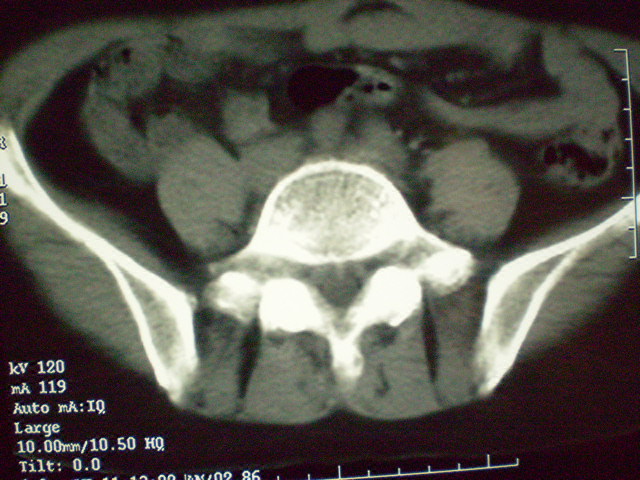

f 60y,b超提示脂肪瘤.[img][/img]

右侧附件囊性畸胎瘤,三种组织均见.

右侧附件囊性畸胎瘤.

那个高密度灶形状好象牙齿。典型,收藏了

脂肪密度肿块,内可见团块状影,典型皮样囊肿

的确比较典型的畸胎瘤!不过,应该确切的说是盆腔畸胎瘤,右侧附件来源的可能性比较大。

有钙化,畸胎瘤